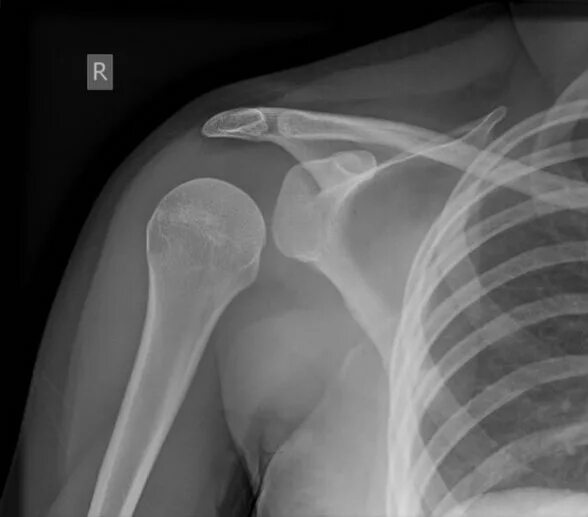

Как выглядит вывих плеча